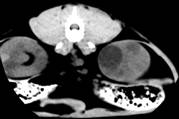

Комп’ютерна томографія нирок у домашніх собак

і кішок,

хворих на полікистоз. Враховуючи той факт, що в

доступній спеціальній літературі не вдалося знайти повідомлень щодо

застосування методу комп’ютерної томографії для діагностики ренальних патологій

у кішок, ми у своїй роботі вважали актуальним вивчення цього питання.

Комп’ютерну томографію застосовували, попередньо

встановивши діагноз з використанням загальних методів, ультрасонографії та

лабораторних досліджень. Дослідження здійснювали за допомогою покрокового

комп’ютерного томографу фірми «Siemens»

Somaton CR-X.

Тварин розміщували на рухомому столі приладу у спинно-черевному положенні, так

щоб під час процедури напрямок руху був краніо-каудальним. Забезпечували

належну фіксацію пацієнта. Томографію проводили при параметрах приладу 120 кV,

80mА у аксіальній

проекції. Визначивши краніальний полюс правої нирки, розпочинали сканування з

інтервалом 3-5 мм, аж до каудального полюсу лівої нирки. Результати аналізували

за допомогою комп’ютера та графічно.

За отриманими даними, полікистозні ураження обох

органів візуалізувались на томограмі у вигляді округлих утворень різної

щільності за шкалою Хаунсфілда, що певною мірою залежить від характеру вмісту

кіст (мал). Так, відносна гіподенсність (10-20 HU)

порожнини кіст може свідчити про низький вміст органічних речовин, що в свою

чергу можна характеризувати як неускладнений перебіг полікистозу. Більш висока

інтенсивність сигналу (50-60 HU)

свідчить про крововилив у кісту. Зростання інтенсивності сигналу у цьому разі,

очевидно, спричинене високим вмістом заліза у гемоглобіні, що й зумовлює зміни

парамагнітних властивостей середовища.

Рис.6. Серія КТ

сканів нирок кота. Кисти нирок, більше зліва